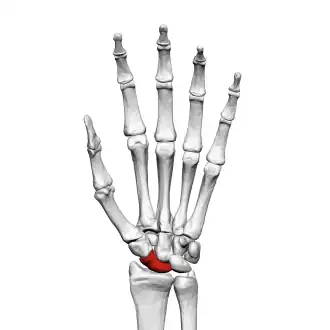

![]() Left hand anterior view (palmar view). Scaphoid bone shown in red. | |

The scaphoid bone is one of the carpal bones of the wrist. It is situated between the hand and forearm on the thumb side of the wrist (also called the lateral or radial side). It forms the radial border of the carpal tunnel. The scaphoid bone is the largest bone of the proximal row of wrist bones, its long axis being from above downward, lateralward, and forward. It is approximately the size and shape of a medium cashew nut.